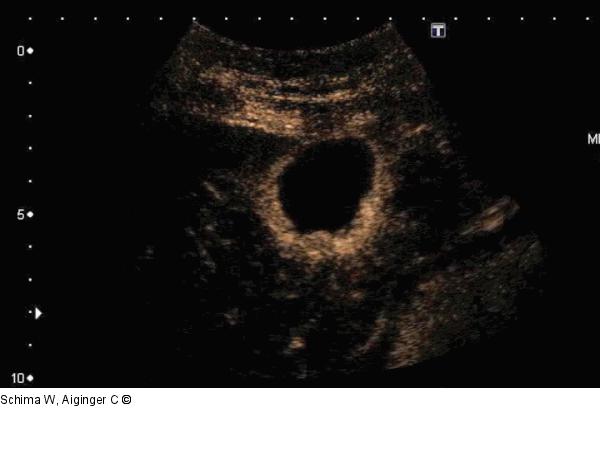

Abbildung 6: Film 2 Kontrastmittelsonographie: Abszessformation in der Leber mit rascher (früharterieller) Kontrastmittelaufnahme in den entzündlichen Randgebieten der Raumforderungen. |

Kontrastmittelsonographie: Abszessformation in der Leber mit rascher (früharterieller) Kontrastmittelaufnahme in den entzündlichen Randgebieten der Raumforderungen. |